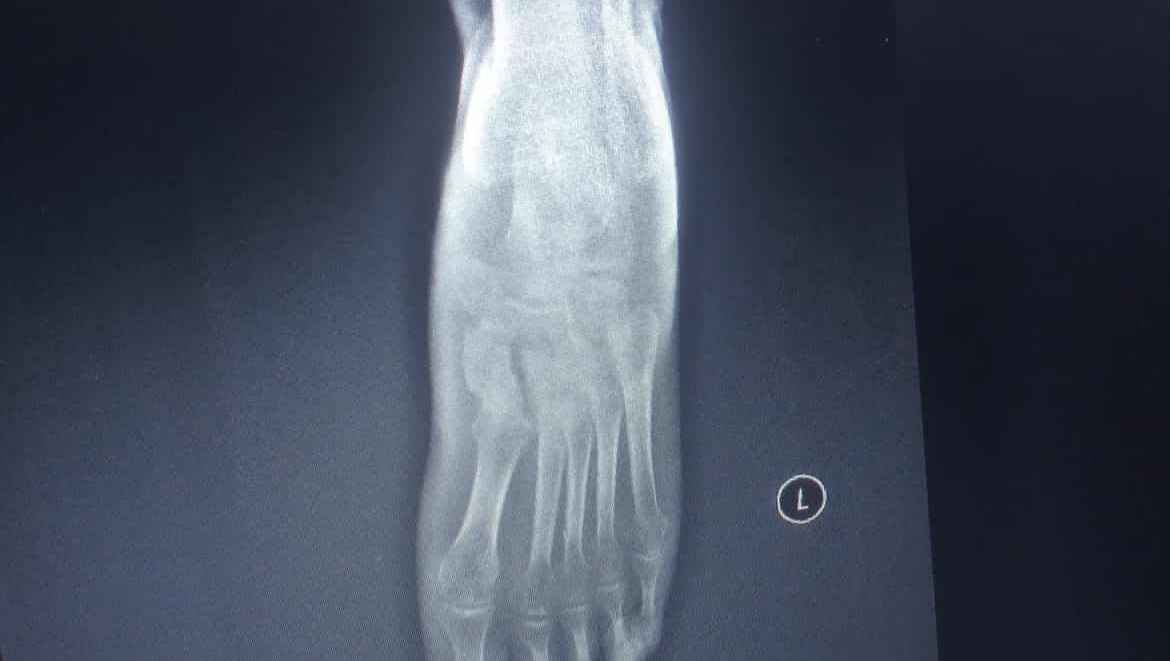

In 2023, my left shoulder suddenly stopped moving, then I started to develop sores on my body in the abdominal area, my right wrist and right leg from behind. I also suffered a fracture in the metatarsal bone of my left foot. However, there was no swelling and the pain was minor. Upon examination, it was found that I had erosion in the foot bone, bone fragility, deformation, and inflammation in the bone marrow. Due to this, I was no longer able to work (something that my family relied on as I used to send them money each month) and because of this I was unable to pay for the medical treatment I needed in Turkey.